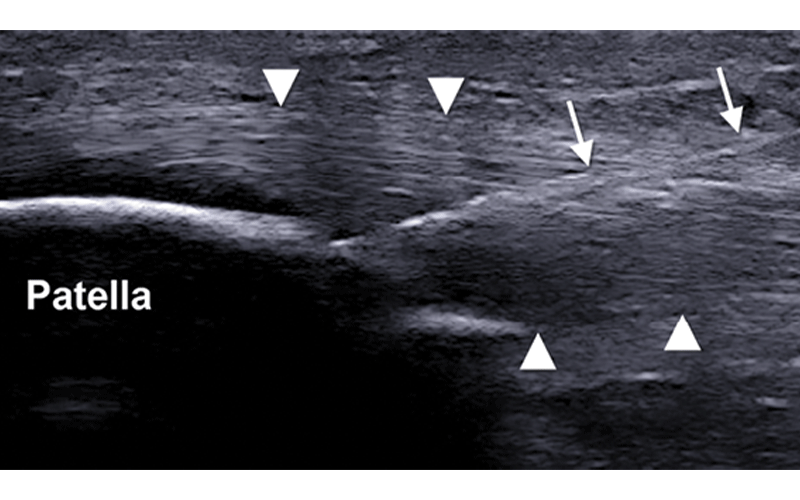

Results from a 2014 study in the American Journal of Sports Medicine on patellar tendinosis showed that, in the short term, PRP was better than dry needling, a technique in which a needle is introduced into the damaged area of the tendon to trigger a healing response. That advantage was lost at about 26 weeks post-treatment.

“If I’m injecting PRP, I’m going to fenestrate the tendon to make space for the PRP,” said Dr. Jacobson, who has published multiple studies on dry needling for chronic tendinosis. “One theory of why PRP and dry needling have similar outcomes is that the underlying process of needling the tendon is present with both procedures.”